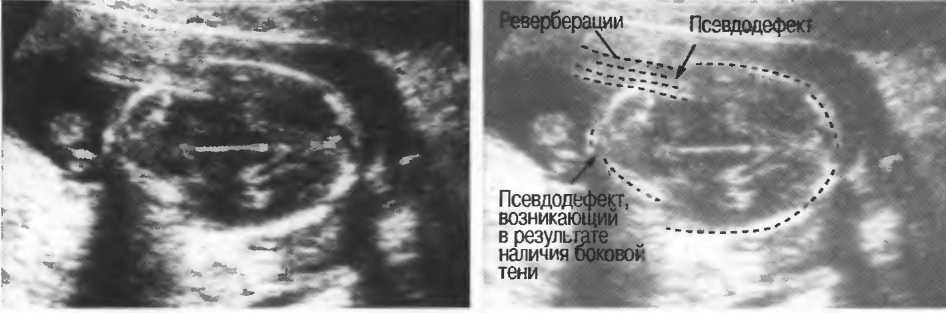

Рис.20г. Тени и реверберации в подкожных слоях головки плода создают иллюзию наличия дефекта черепа.